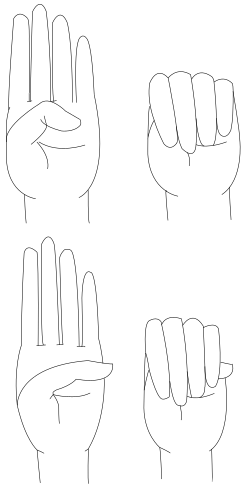

The Steinberg sign, also known as the thumb sign, is one of the clinical examination tests for Marfan disease in the hands. It is a clinical test in which the tip of the thumb extends beyond the palm when the thumb is clasped in the clenched hand.[13][14][15]

- Wrist AND thumb sign = 3 (wrist OR thumb sign = 1)

The thumb sign (Steinberg's sign) is elicited by asking the person to flex the thumb as far as possible and then close the fingers over it. A positive thumb sign is where the entire distal phalanx is visible beyond the ulnar border of the hand, caused by a combination of hypermobility of the thumb as well as a thumb which is longer than usual.

The wrist sign (Walker-Murdoch sign) is elicited by asking the person to curl the thumb and fingers of one hand around the other wrist. A positive wrist sign is where the little finger and the thumb overlap, caused by a combination of thin wrists and long fingers.[60]